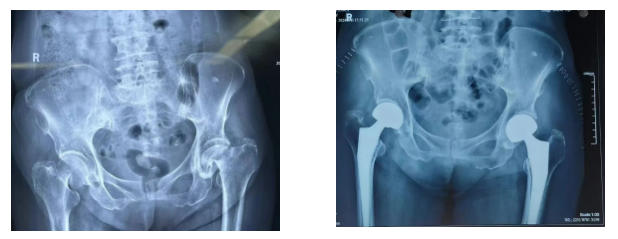

家住西影路的唐老太(化名)今年83岁,一个月内先后不慎摔倒了两次,结果导致左右两侧股骨颈均骨折,这使得她无法下地行走,就连翻身都极为困难。在家人陪同下来到陕西冶金医院骨科就诊。

▲术后第三天即可下床行走

考虑到老人年龄较大且左右两侧股骨颈均骨折,为避免二次手术带来的多重创伤,骨科主任赵学刚决定一次手术解决两侧问题。同期行双侧人工股骨头置换术,成功为她替换了双侧髋关节,手术过程十分顺利。术后第三天就能下地功能锻炼。老人和家属非常满意,对骨科医护人员精湛技术及悉心护理更是高度认可。出院后,特地为骨科送来了锦旗,以此表达诚挚谢意。